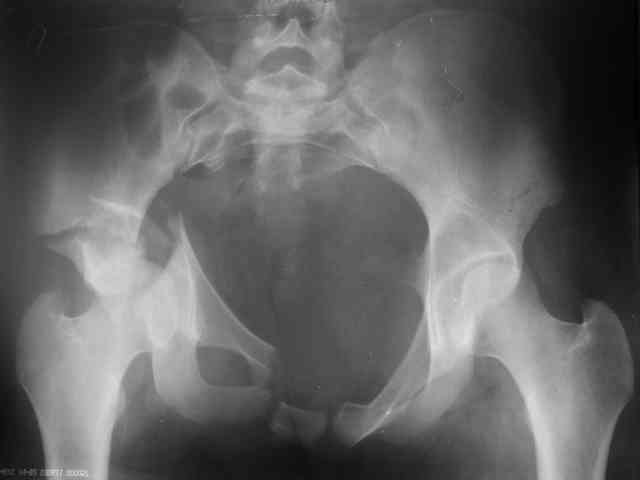

Re: acetabular fracture

P.S. в приложении R пациентки с похожей проблемой доступа.. за исключением того, что перелом

двухколонный. Вертлугу лечили Y доступом.